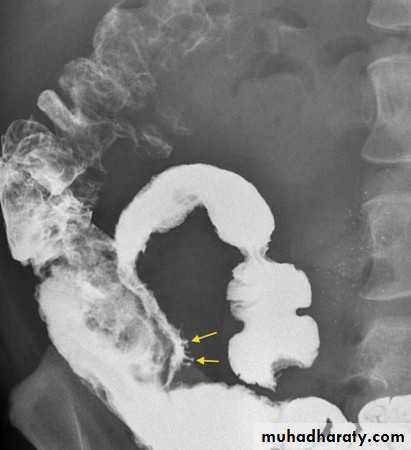

Diverticular disease:

Out-pouching of the mucosa through the muscular layer of the bowel wall

Very common particularly in adults, commonest in the sigmoid.

The diverticulae when filled with barium produce a spherical out-pouching with an narrowed neck (diverticulosis), some pouches do not fill with barium when inflamed (diverticulitis) causing symptoms such as sepsis, diarrhea or obstruction.

The colon may show "saw tooth serrated" appearance from muscle hypertrophy.

More extensive lesions produce perforation with fistulae into the bladder, SI or vagina,Pericolic abscess and sometimes pneumoperitoneum.

A stricture may occur in an area of recognizable diverticular disease otherwise canot be differentiated from carcinoma.